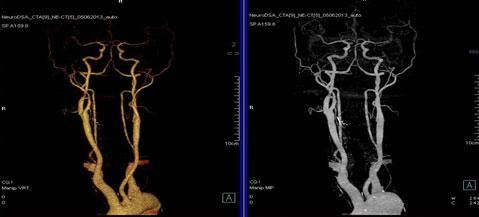

二、多層螺旋CT頭頸部及體部血管成像技術:

該機掃描覆蓋範圍廣、時間短,多種後處理分析軟件能顯示各血管細小分支,可以清晰顯示動脈瘤、動脈夾層、血管畸形、血管狹窄及動脈粥樣硬化斑塊等,适用于頭頸部血管成像、肺動脈成像、胸腹部血管成像及四肢血管成像。

1.顱腦血管成像:

動脈瘤

2、頸部血管成像

3、肺動脈血管成像:

4、腎動脈血管成像(腎動脈狹窄):

5、下肢動脈血管成像: